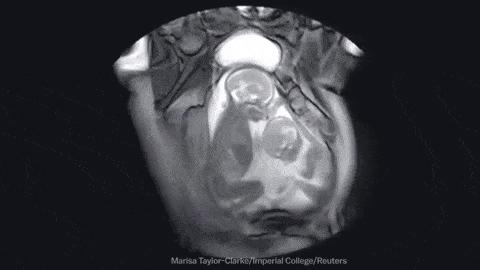

罗伯洛赫尔开启对核磁共振的研究并得到放射

学界众所周知的核磁共振图像诺丁汉的橙子

1978年组建了团队开展“质子项目”的研究

并拥有了当时世界上最强大的一台长达1米的

0.15T磁体。1980年12月3号得到了第一幅

人类头部核磁共振图像后来,在优化了

序列设计后,他们又获得了体部图像

放射科医生也第一次看到了可分辨的器官

丁汉的橙子和首次头颅 MR 成像